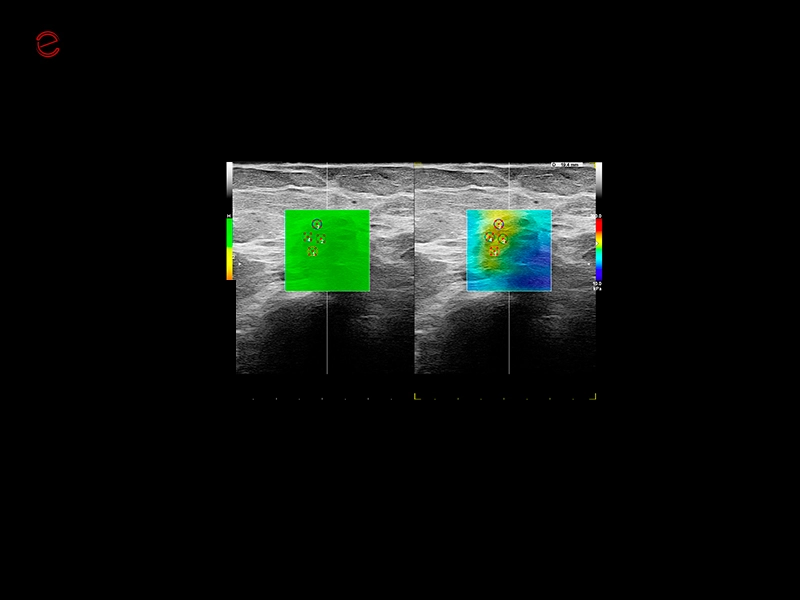

MyLab™9 Platform - Dual ElaXto characterization on breast lesion

MyLab™9 Platform - Dual ElaXto characterization on breast lesion